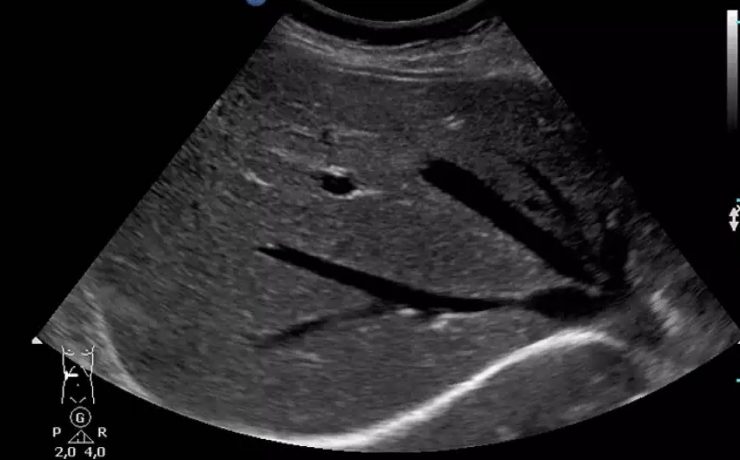

Las bacterias pueden afectar a la función hepática por invasión biliar o del parénquima, o como manifestación sistémica de bacteriemia o endotoxemia. La afectación hepática puede variar desde alteraciones mínimas de las pruebas de función hepática hasta el fallo hepático con insuficiencia hepatocelular severa. Repercusión